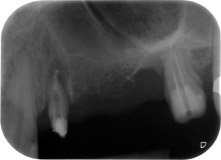

Nach einer lokalen Applikation von 25-prozentigem Metronidazol-Gel (Elyzol) in die Taschen des Zahns 24 wurde die ursächliche Behandlung mit systematischer Parodontaltherapie einschließlich Full-Mouth-Disinfection begonnen. Die orthograde Wurzelkanalbehandlung wurde mittels einer thermoplastischen Obturation mit Guttapercha, einem Glasfaserstift und einem Komposit-Stumpfaufbau revidiert (Abb. 2). Die Brücke wurde außer Okklusion wieder befestigt, um die ungestörte Heilung der GTR- und GBR-Bereiche zu gewährleisten.

Einen Monat nach dem Eingriff waren sowohl die Schmerzen als auch die Entzündung an Zahn 24 minimal, die Zahnbeweglichkeit lag jedoch noch bei Miller-Klasse 2. Nach Freilegung und Reinigen des infizierten periapikalen und periradikulären Gewebes wurde das Ausmaß des Knochendefizits deutlich (Abb. 2 und 3).